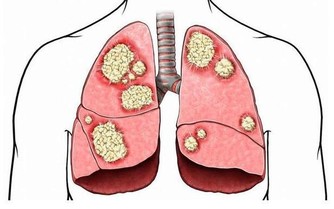

小腿靜脈曲張是最重要的疾病之一, 也是四肢血管疾患中最常見的疾病之一。

靜脈曲張是指由於血液淤滯、靜脈管壁薄弱等因素,導致的靜脈迂曲、擴張。

由於先天性血管壁膜比較薄弱或長時間維持相同姿勢很少改變,血液蓄積下肢,

在日積月累的情況下破壞靜脈瓣膜而產生靜脈壓過高,是血管突出皮膚表面的症狀。